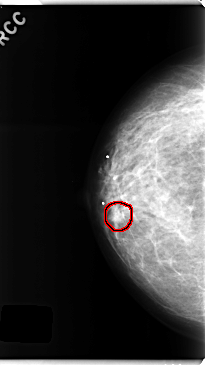

C_0252_1.RIGHT_CC

FILE: C_0252_1.RIGHT_CC.OVERLAY

TOTAL_ABNORMALITIES 1

ABNORMALITY 1

LESION_TYPE MASS SHAPE OVAL MARGINS MICROLOBULATED

ASSESSMENT 4

SUBTLETY 4

PATHOLOGY BENIGN

TOTAL_OUTLINES 1

BOUNDARY